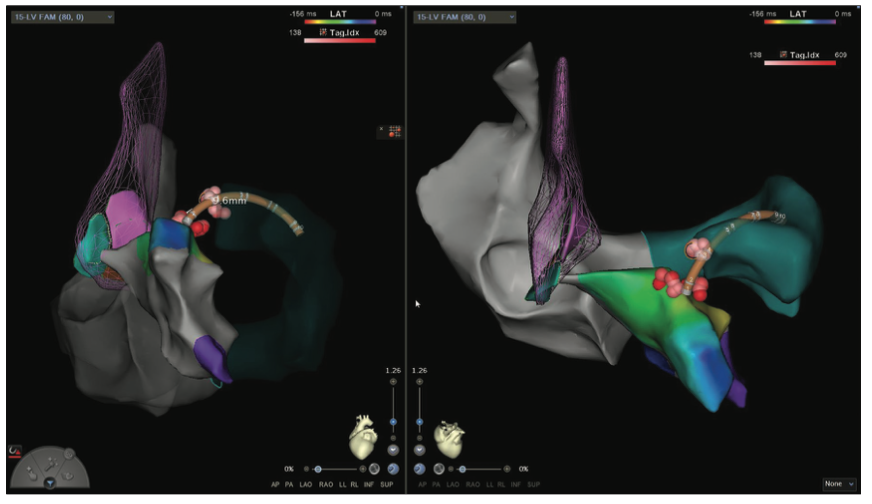

Videos 13a-b and Figure 13c demomstrate a zero fluoroscopic ischemic, incessant, hemodynamically tolerated VT ablation and creation of a 4-chamber EAM/sound map and a figure-of-8 VT in a patient with a large anteroapical infarction along with the electrogram resolution afforded by small 1-mm electrodes of the Pentaray in the isthmus corridor.